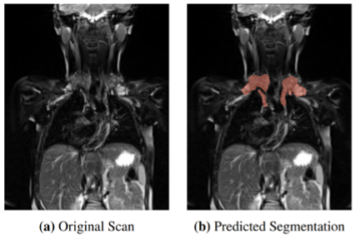

The new tool automates the complex and time-consuming process of annotating lymphatic perfusion patterns in MRI scans and supports the classification of lymphatic perfusion patterns by clinicians. This innovation promises to streamline clinical workflows, improve long-term patient monitoring, and enhance patient care by enabling precise and rapid assessments.